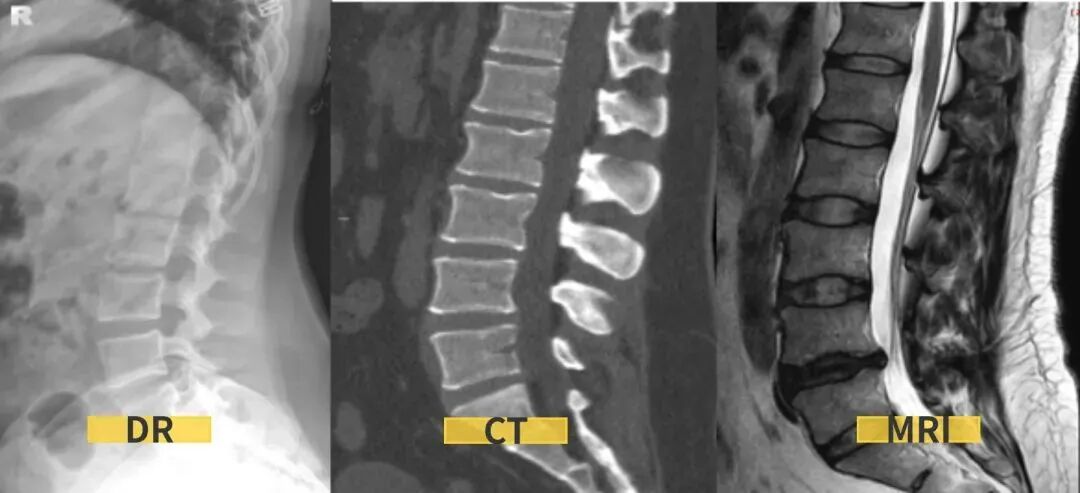

一、X线:往往是初步检查的首选。腰椎的X线检查一般拍摄腰椎正侧位,还有双斜位和过伸过屈位;

优点:主要用来观察腰椎的骨质情况,可观察到腰椎曲度、增生、椎体滑脱、峡部裂、肿瘤、腰椎骨折等。

缺点:X线检查不能显示软组织结构,如椎间盘、神经根、肌肉等。对腰椎间盘突出或者神经根受压的诊断价值不大。另外,X光是有一定辐射剂量的,不适合孕妇及反复拍摄。

二、CT:也是利用x光扫描,可以围绕人体360度无死角的进行扫描。

优点:CT扫描能观察到横断面的细节,能了解腰椎的骨质情况、椎间盘突出和硬膜囊神经根的关系,椎间关节之间的情况等;可以做到薄层几百幅图像能更好的看清细小的病变,特别是微小的骨折;在扫描结束后可以通过影像后处理的方法,把腰椎图像重建成矢状位或冠状位,可从多个平面的不同角度去观察腰椎的影像情况。

三、核磁共振(MRI):这是一种利用强磁场和射频信号的高级检查方法。

优点:磁共振检查在软组织成像上更胜于腰椎CT。可以很好地观察腰椎间盘的情况,更清晰地显示椎间盘的形态及其与硬膜囊、神经根等周围组织的关系。在脊髓病变、炎性病变、出血性病变及腰部肌肉病变等方面也具有优势。此外,磁共振检查不存在X线辐射,是较为安全可靠的检查。

缺点:价格较高,时间较长,有明确的限制人群,如有金属植入物、胰岛素泵或者心脏起搏器的患者。此外,因磁共振机器的孔径一般都不是很大,所以患有幽闭恐惧症的患者,也不建议首选腰椎MRI。

最后,简单总结下,如果您只是轻微的腰痛,没有神经根受压的迹象(如下肢放射痛、麻木等),可以先做X线检查;如果有外伤或是评估骨质结构或是否有钙化,建议做CT检查;如果有神经根受压、软组织损伤或者怀疑肿瘤等严重情况,建议做MRI检查。

腰椎的X线、CT和MRI三项检查,是不能够互相代替的。不管是腰椎X光片还是CT或者MRI,这三项检查都有它们各自的优缺点。就诊时医生需要通过查体,结合临床症状,才能为患者选出最合适的检查。